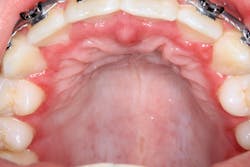

A healthy 16-year-old male presented with this chief complaint: I got my wisdom teeth out five days ago, and I can’t eat or swallow; it hurts. I have bumps all over in my mouth.

Clinical assessment revealed multiple white lesions with red borders salt-and-peppered in a generalized fashion throughout the entire oral cavity. The gum tissues were swollen and any light palpation/touching of the lesions resulted in bleeding and pain. See clinical photos below.

Acute herpetic gingivostomatitis